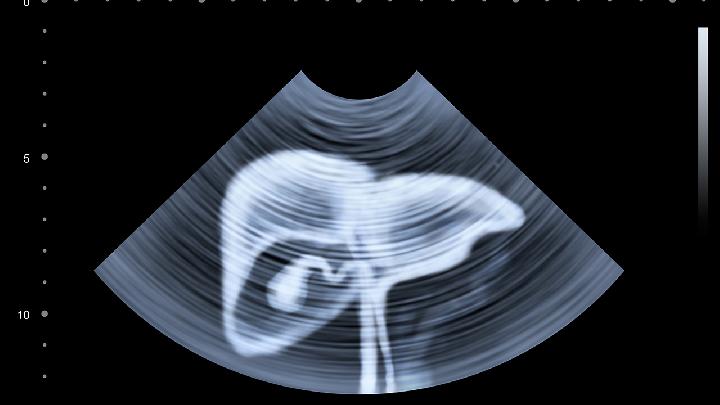

1、妇科疾病:常见于盆腔炎等,常伴有白带性状变化、腰酸腰痛、下腹坠胀感,通过B超检查及血、白带培养检查一般可明确诊断。可能需要使用阿莫西林、甲硝唑、康妇消炎栓等药物治疗;如果有同房史并且月经延迟,下体有血,需排除宫外孕可能,行盆腔B超检查,并且尽早去医院行手术治疗,以免造成大出血休克;

2、胃肠炎:常见不洁饮食、暴饮暴食,因饮食习惯不好,如喜食辛辣刺激食物,或肠道慢性炎症等,可导致肠黏膜受到刺激,引发肠痉挛,出现疼痛;长期便秘患者,也可能会出现腹部刺痛症状,常常伴有反酸、烧心、腹泻等消化不良症状。一般通过血检、大便常规、腹部彩超、X线等检查可帮助诊断,建议清淡饮食、食用易消化食物,还可使用药物治疗,如左氧氟沙星片、盐酸洛哌丁胺胶囊等;

3、泌尿系感染或是泌尿系结石:因细菌感染或结石刺激,导致输尿管平滑肌收缩、痉挛,出现腹部刺痛,多为单侧,可以化验尿常规及做泌尿系的B超检查明确诊断。感染者一般服用阿莫西林、头孢克洛、左氧氟沙星等药物;结石患者通常服用排石冲剂、枸橼酸氢钾钠等药物;平时可多喝水,还可使用阿托品、吲哚美辛等药物缓解疼痛。